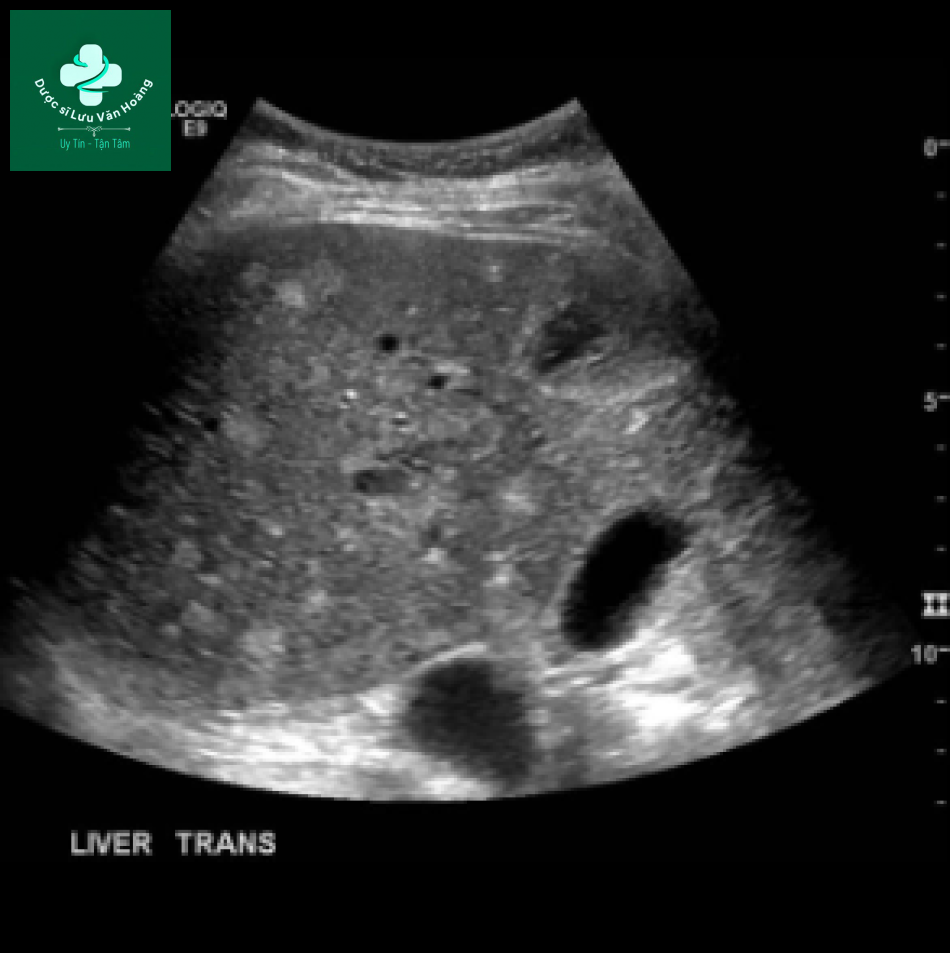

Siêu âm

Có thể thấy giãn đường mật trong gan Các vách âm đi ngang qua lòng ống mật bị giãn. Các nhánh tĩnh mạch cửa nhỏ được bao quanh một phần hoặc hoàn toàn bởi đường mật giãn: dấu hiệu “intraluminal portal vein”. Sỏi trong đường mật.

Đa u mô thừa đường mật. Hình ảnh siêu âm cho thấy nhiều tổn thương tròn nhỏ tăng âm trong gan, với một số ít tổn thương lớn giảm âm.